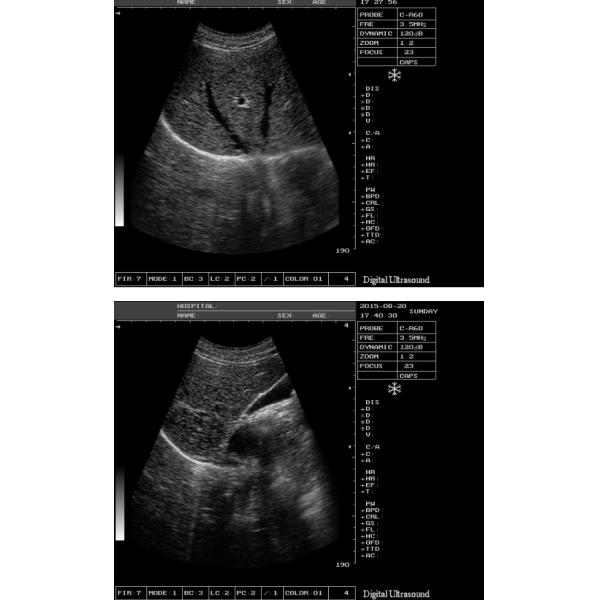

| Режимы работы монитора | выпуклый зонд массива 3.5MHz/R60: B, B/B, 4B, B+M, m |

| Dimpling зонд массива 6.5MHz/R13: B | |

| 7,5 MHz/L40 линия зонд массива: B | |